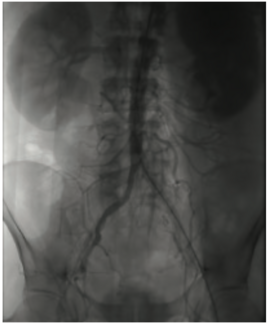

An 80-year-old female with a history of heart failure with reduced ejection fraction, hypertension, and chronic kidney disease presented with worsening dyspnea and fatigue for 6 months despite being on optimal guideline-directed medical...